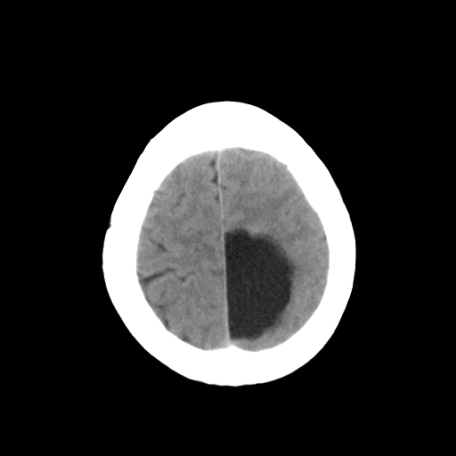

以下是引用深泽交通医院在2009-8-7 12:18:00的发言:[br]有壁结节,考虑囊变型胶质瘤

以下是引用卜一在2009-8-7 15:50:00的发言:[br]囊变性脑膜瘤!支持!

以下是引用随光逐影在2009-8-7 15:58:00的发言:[br]考虑左侧顶叶胶质瘤,不排除左侧镰旁脑膜瘤;建议行进一步检查。